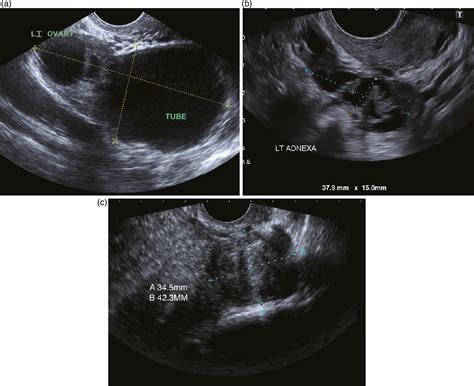

Defining a Normal Ovary Ultrasound

When a radiologist or sonographer reviews a normal ovary ultrasound, they are looking for specific anatomical markers. It is important to remember that ovaries change throughout the menstrual cycle and across a person's lifespan, so "normal" can look different depending on your age and hormonal status.

Key characteristics of healthy, normal ovaries include:

• Size and Volume: Ovaries should be within a normal volume range. In premenopausal individuals, a healthy ovary is typically around 3 to 5 centimeters in length.

• Texture and Echogenicity: The internal texture (echotexture) should appear uniform. It should not show solid masses or irregular fluid pockets that suggest pathology.

• Follicular Activity: It is entirely normal to see small, fluid-filled sacs known as follicles. These are where eggs develop. The presence of several small follicles is a sign of healthy ovarian function.

• Position: The ovaries should be located in their expected anatomical position within the pelvis, typically lateral to the uterus.

When you receive the results of your normal ovary ultrasound, you might see medical terminology that seems confusing. Phrases like "normal echotexture" or "no adnexal masses seen" are excellent indicators. "Adnexa" refers to the area near the uterus, which includes the ovaries and fallopian tubes. Therefore, seeing "no adnexal masses" simply means the technician did not find any abnormal lumps, growths, or suspicious cysts in that area.